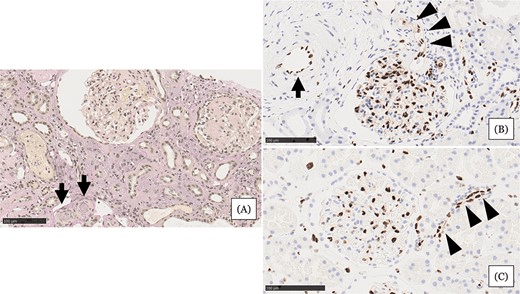

- 腎活檢示小動(dòng)脈嚴(yán)重狹窄或阻塞,內(nèi)皮損害嚴(yán)重,腎小球萎縮,間質(zhì)細(xì)胞浸潤(rùn)(圖1A)

- 與血壓正常的正常腎組織相比,血管內(nèi)皮細(xì)胞(EC)細(xì)胞核等長(zhǎng)排列整齊(圖1C)

- 患者腎組織中EC細(xì)胞核大小不一,細(xì)胞核明顯,小動(dòng)脈內(nèi)細(xì)胞核較少(圖1B)